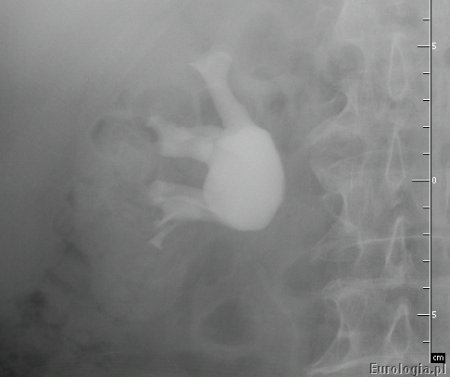

Zwężenie połączenia miedniczkowo - moczowodowego